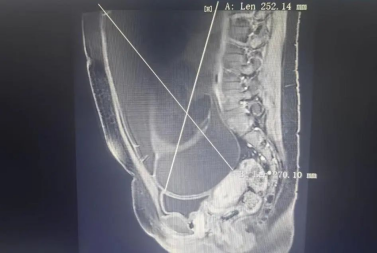

经检查,发现患者盆腹腔有一巨大囊性团块,导致患者腹隆如怀孕足月。由于巨大包块的压迫,出现右侧肾积水,右侧输卵管上段扩张。

妇产科副主任医师孟亚萍介绍,患者盆腔肿物较大,占据了盆腹腔大部分空间,手术风险和难度均较大。直径29厘米的肿瘤该如何进行手术呢?万一是恶性怎么办?如果开腹手术切口肯定很大、恢复期很长,会留下难看的瘢痕,患者能接受吗?日后还有恋爱生子的压力,这一侧卵巢是否可以保留呢?......种种未知,不仅对医生来说是严峻的挑战,也让患者小美和父母焦虑得数晚失眠。